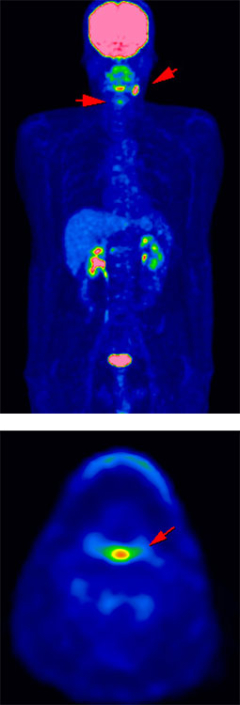

治療後経過観察にて以前の病変近傍に新たな病変出現(再発)

悪性リンパ腫